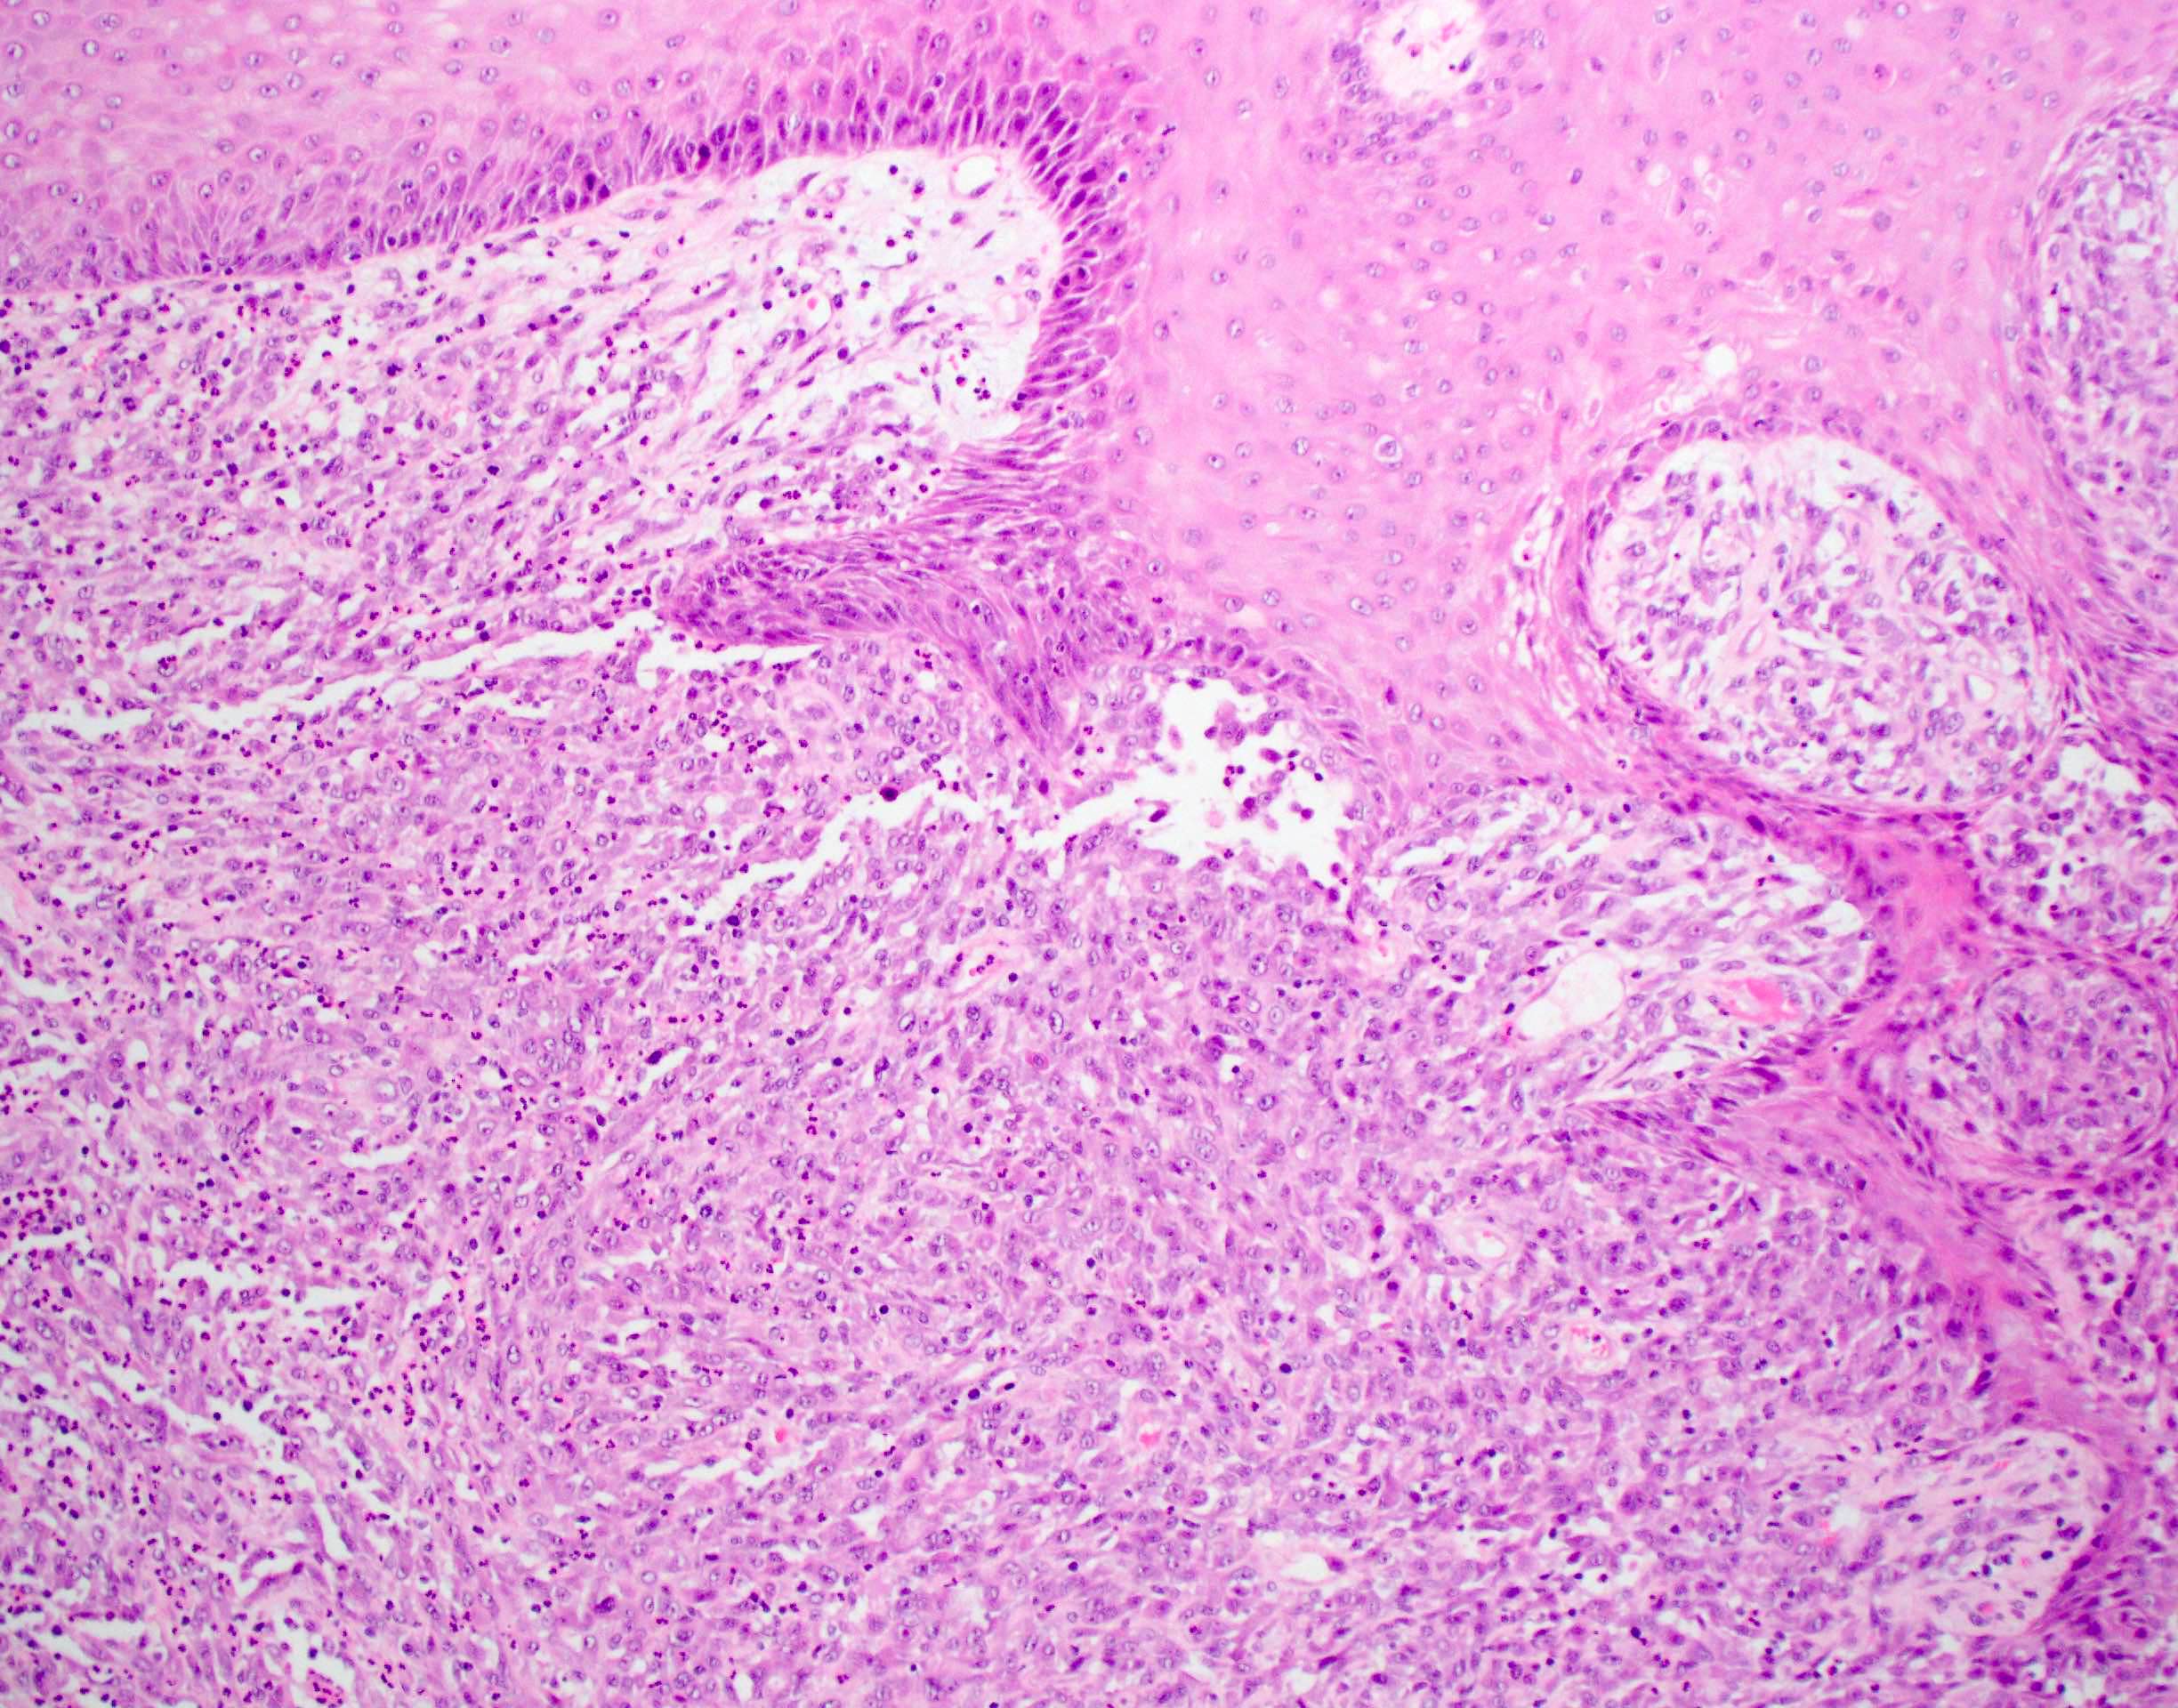

Microscopic (histologic) description

- Squamous cell carcinoma, conventional

- Most common and typical morphology of conventional keratinizing squamous cell carcinoma at any site

- Large polygonal malignant cells with intercellular bridges

- Cytoplasmic or extracellular eosinophilic keratin

- Dyskeratotic cells and squamous pearls

- Nuclear size, pleomorphism, hyperchromasia and mitoses increase with increasing grade

- Verrucous carcinoma

- Pronounced exophytic growth of well differentiated squamous epithelium

- Bulbous enlargement of the rete ridges with elephant foot appearance

- Broad pushing border

- Does not metastasize; good prognosis

- Papillary squamous cell carcinoma

- Well differentiated keratinocytes forming exophytic organized papillary structures with fibrovascular cores

- 70% of tumor must show papillary architecture

- Better prognosis than conventional squamous cell carcinoma

Microscopic (histologic) images

Contributed by Ruta Gupta, M.B.B.S., M.D.